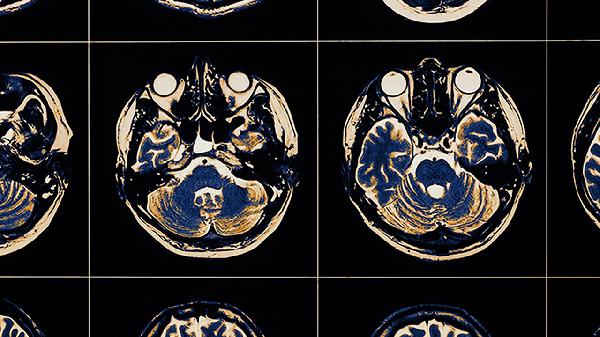

神经可塑性是大脑修复的关键机制。早期持续的心理创伤可能导致前额叶皮层、海马体等区域结构改变,影响情绪调节与记忆功能。针对性心理干预如认知行为治疗能重建负面认知模式,眼动脱敏与再加工治疗可缓解创伤记忆的生理反应。部分患者可能出现杏仁核过度活跃导致的焦虑反应,通过正念训练结合血清素再摄取抑制剂类药物可调节神经递质平衡。社会支持系统重建能促进催产素分泌,减弱创伤相关的应激反应。

严重创伤可能造成下丘脑-垂体-肾上腺轴持续亢进,导致糖皮质激素受体表达异常。这类情况需结合神经反馈治疗与长效抗抑郁药物干预,但部分神经连接改变可能难以完全逆转。儿童时期遭受躯体虐待者可能出现胼胝体发育异常,成年后通过经颅磁刺激治疗可改善左右脑信息整合功能。创伤后应激障碍患者的海马体积缩小现象,在规范治疗后可能出现一定程度再生。